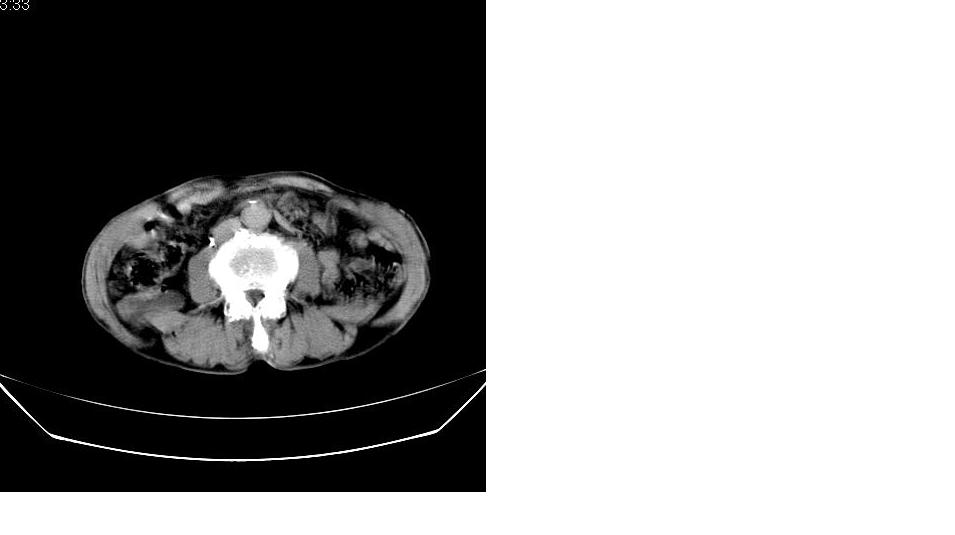

男,76岁,上腹部疼二天来就诊,彩超提示肝左叶占位,随后做上腹部ct平扫,今天做上腹部ct增强扫描,手工推药,效果不好,请谅解。

肝内胆管积气扩张,胆囊增大,肝右前叶低密度灶,逐渐强化,一元论,胆系感染,局限性肝脓肿;右肾囊肿。

考虑肝s4段肝脓肿可能?未排除肝癌。右肾上极囊肿。